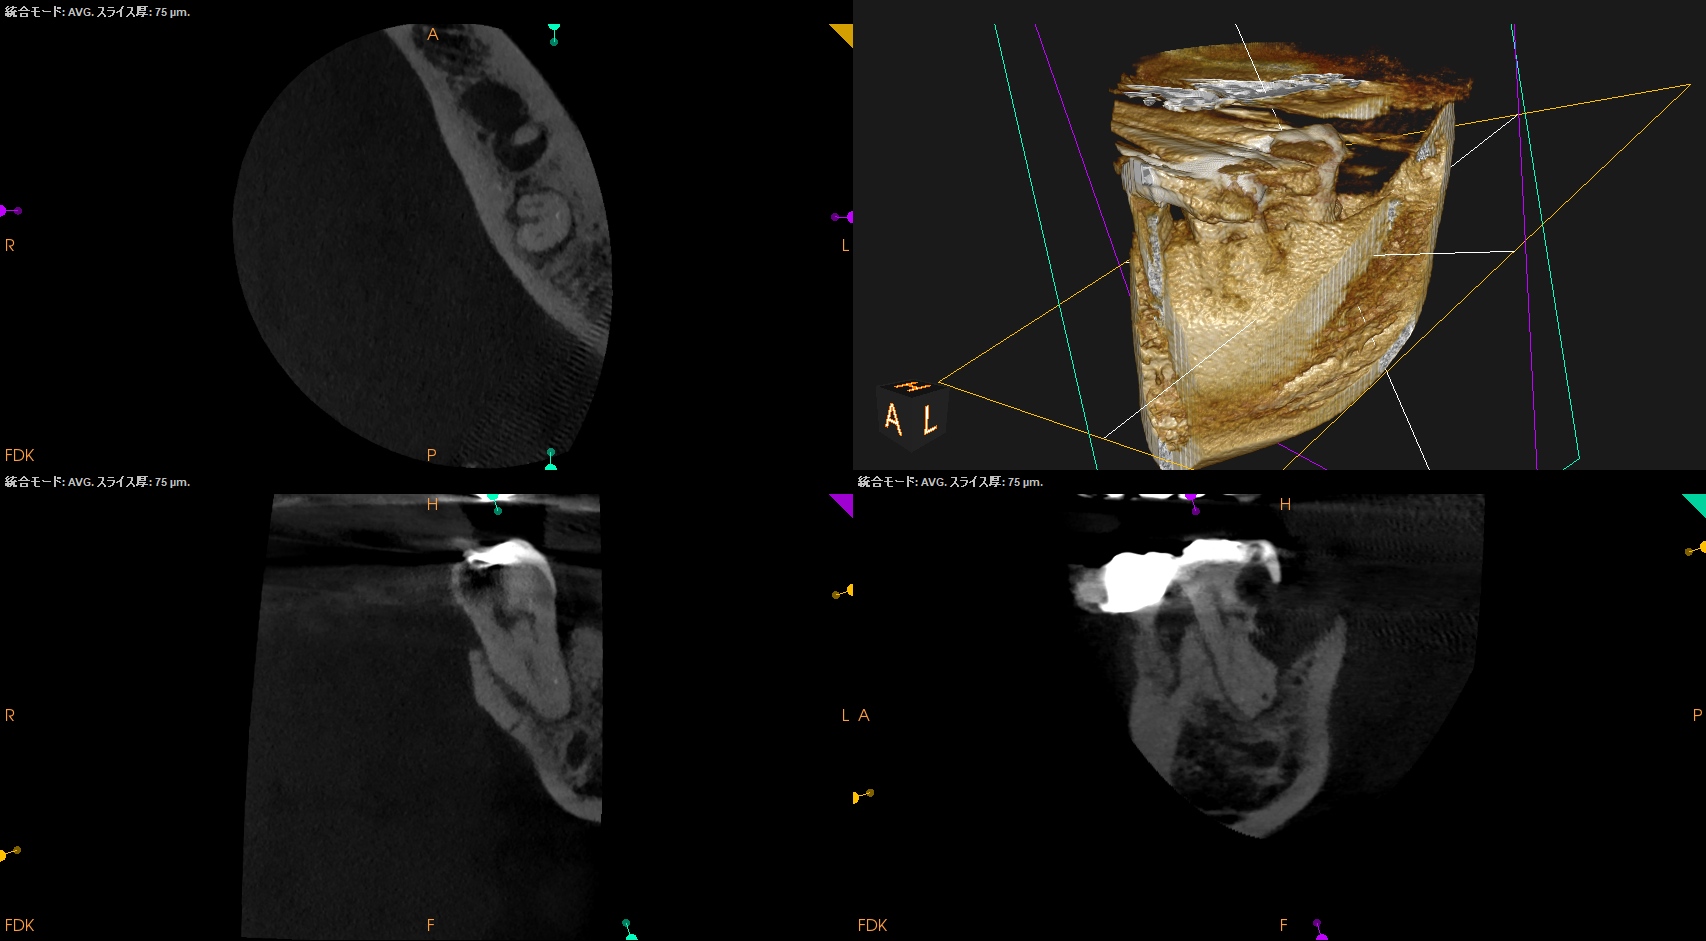

CBCT(2025.12.10)

ML

MB

D

遠心方向から見ると、

絶望的な状態であることがわかる。